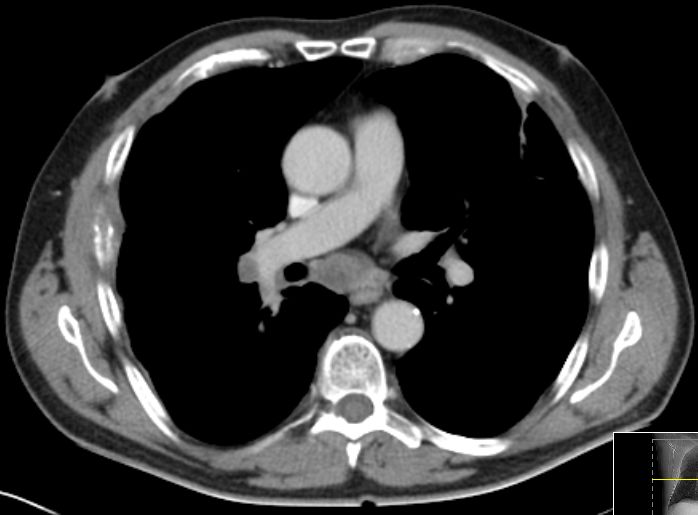

CT Infiltration des oberen Mediastinums. Flottierender Thrombus in der Vena cava superior.